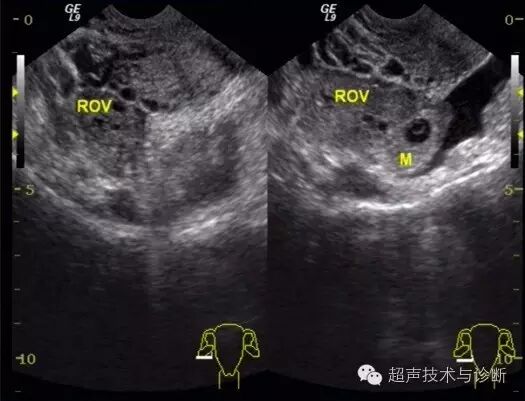

4、超声检查如下(2016。02。01):子宫形态大小正常,宫腔内见一不规则囊性结构,大小4x2cm,透声差,未见双环征及胚芽结构,CDfi未见血流。双侧卵巢可见,右侧附件区可见一囊性结构,大小3x2cm,其内可见胚芽及心管博动。

入院血HCG及超声检查图像如下;